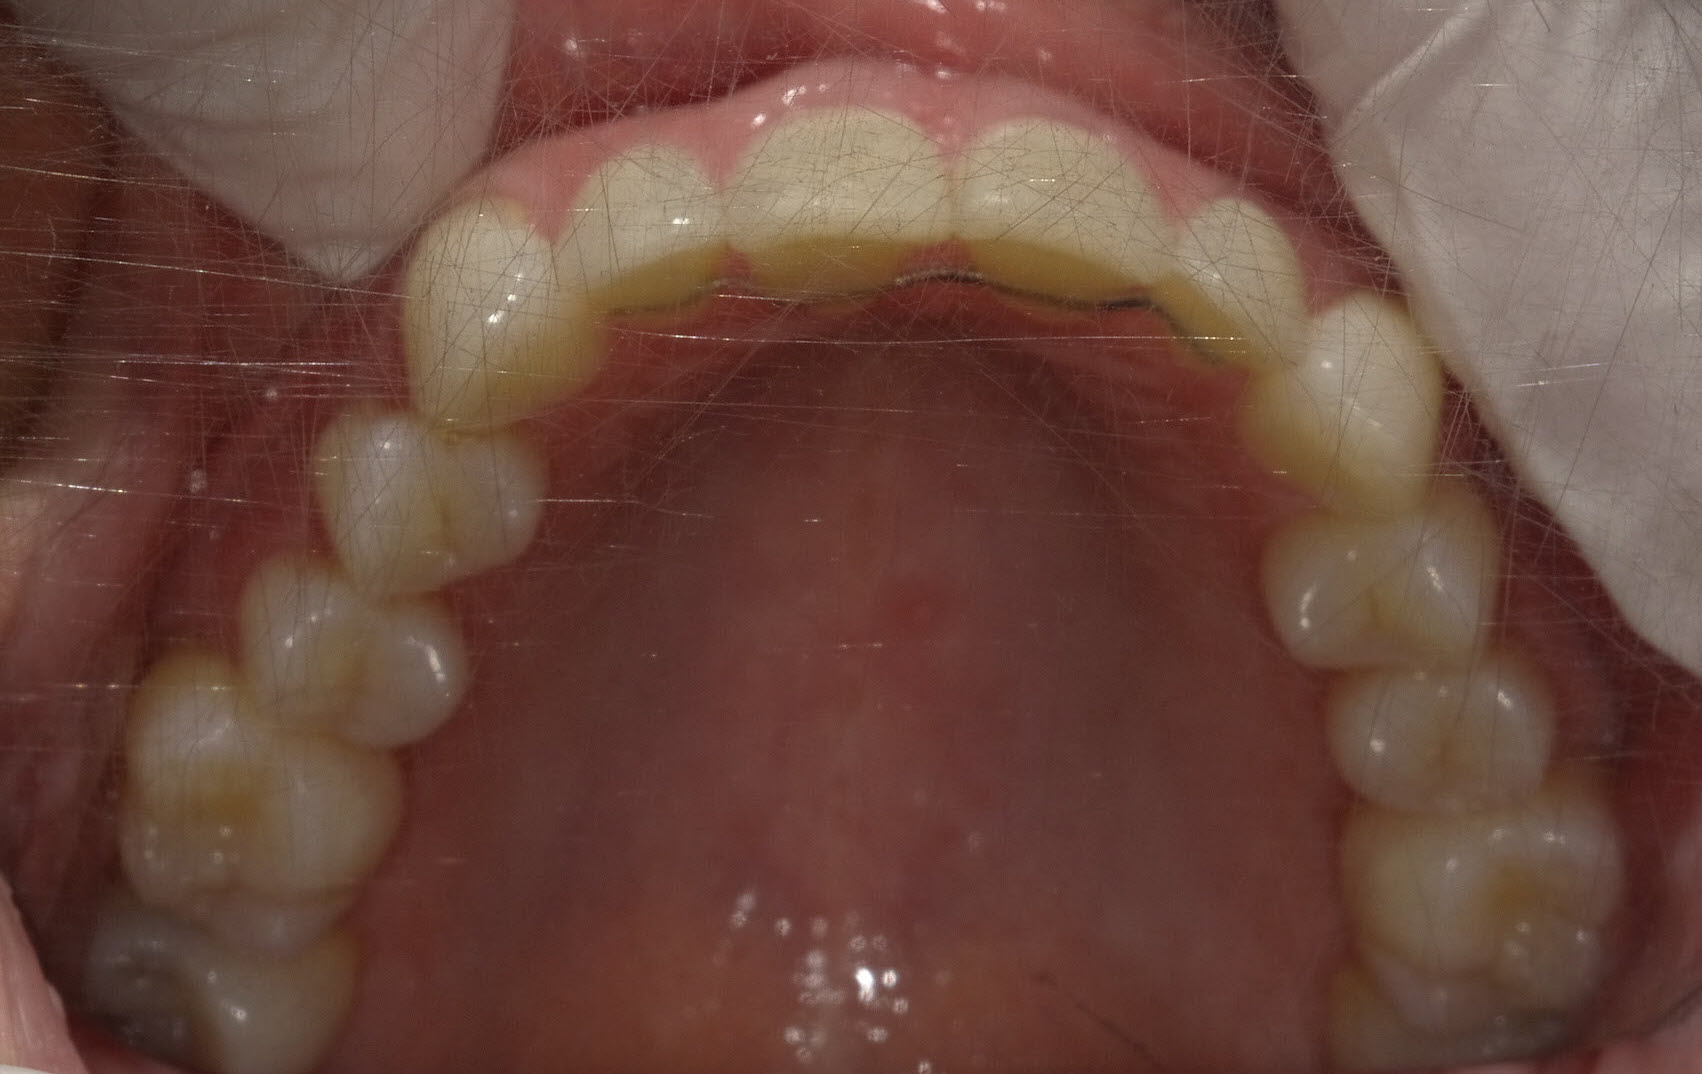

Nach der Behandlung

(Dauer der aktiven Behandlung: Im Oberkiefer 7 Monate, im Unterkiefer 1 Jahr, 4 Monate)